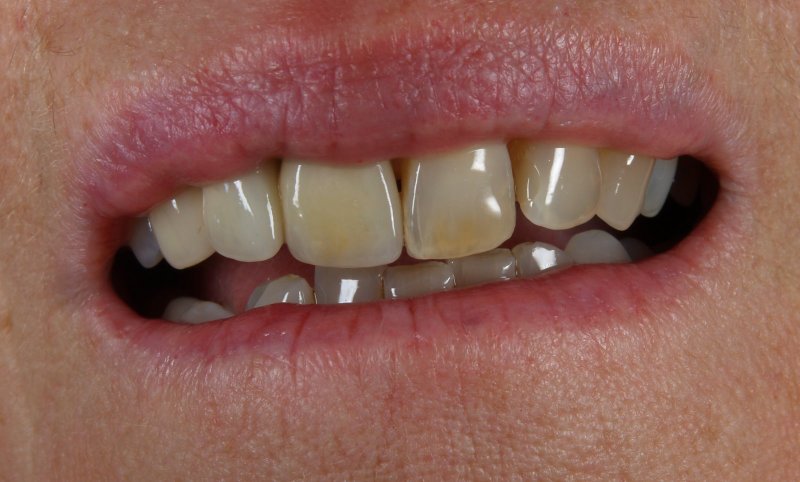

Patientenzufriedenheit